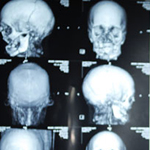

لأول مرة في العالم استطاع فريق طبي بإجراء عملية زرع لوجه كامل. اعلن رئيس الطاقم الطبي خوان بيري باريت ان الاطباء الاسبان اجروا اول عملية في العالم لزرع وجه كامل. واجرى طاقم مكونا من 30 خبيرا عملية زرع الوجه في مستشفى فال دي هيبرون في برشلونة لشاب اصيب في حادث قبل خمس سنوات. واوضح باريت ان المريض لم يكن يستطيع التنفس او البلع او التحدث على نحو مناسب.

وجرى زرع عضلات وجه وجلد وانف وشفاه وفك واسنان وحنك وعظام خدود للشاب في العملية التي استغرقت 22 ساعة واجريت له في العشرين من آذار الماضي واضاف باريت ان حالة المريض جيدة. واشار الطبيب الى ان من المتوقع ان يتمكن الشاب من العيش بشكل طبيعى بعد تماثله للشفاء من العملية. وقال الطاقم الطبي الاسباني ان عشر عمليات لزرع وجه جرت في جميع انحاء العالم ولكن كلها كانت عمليات جزئية.